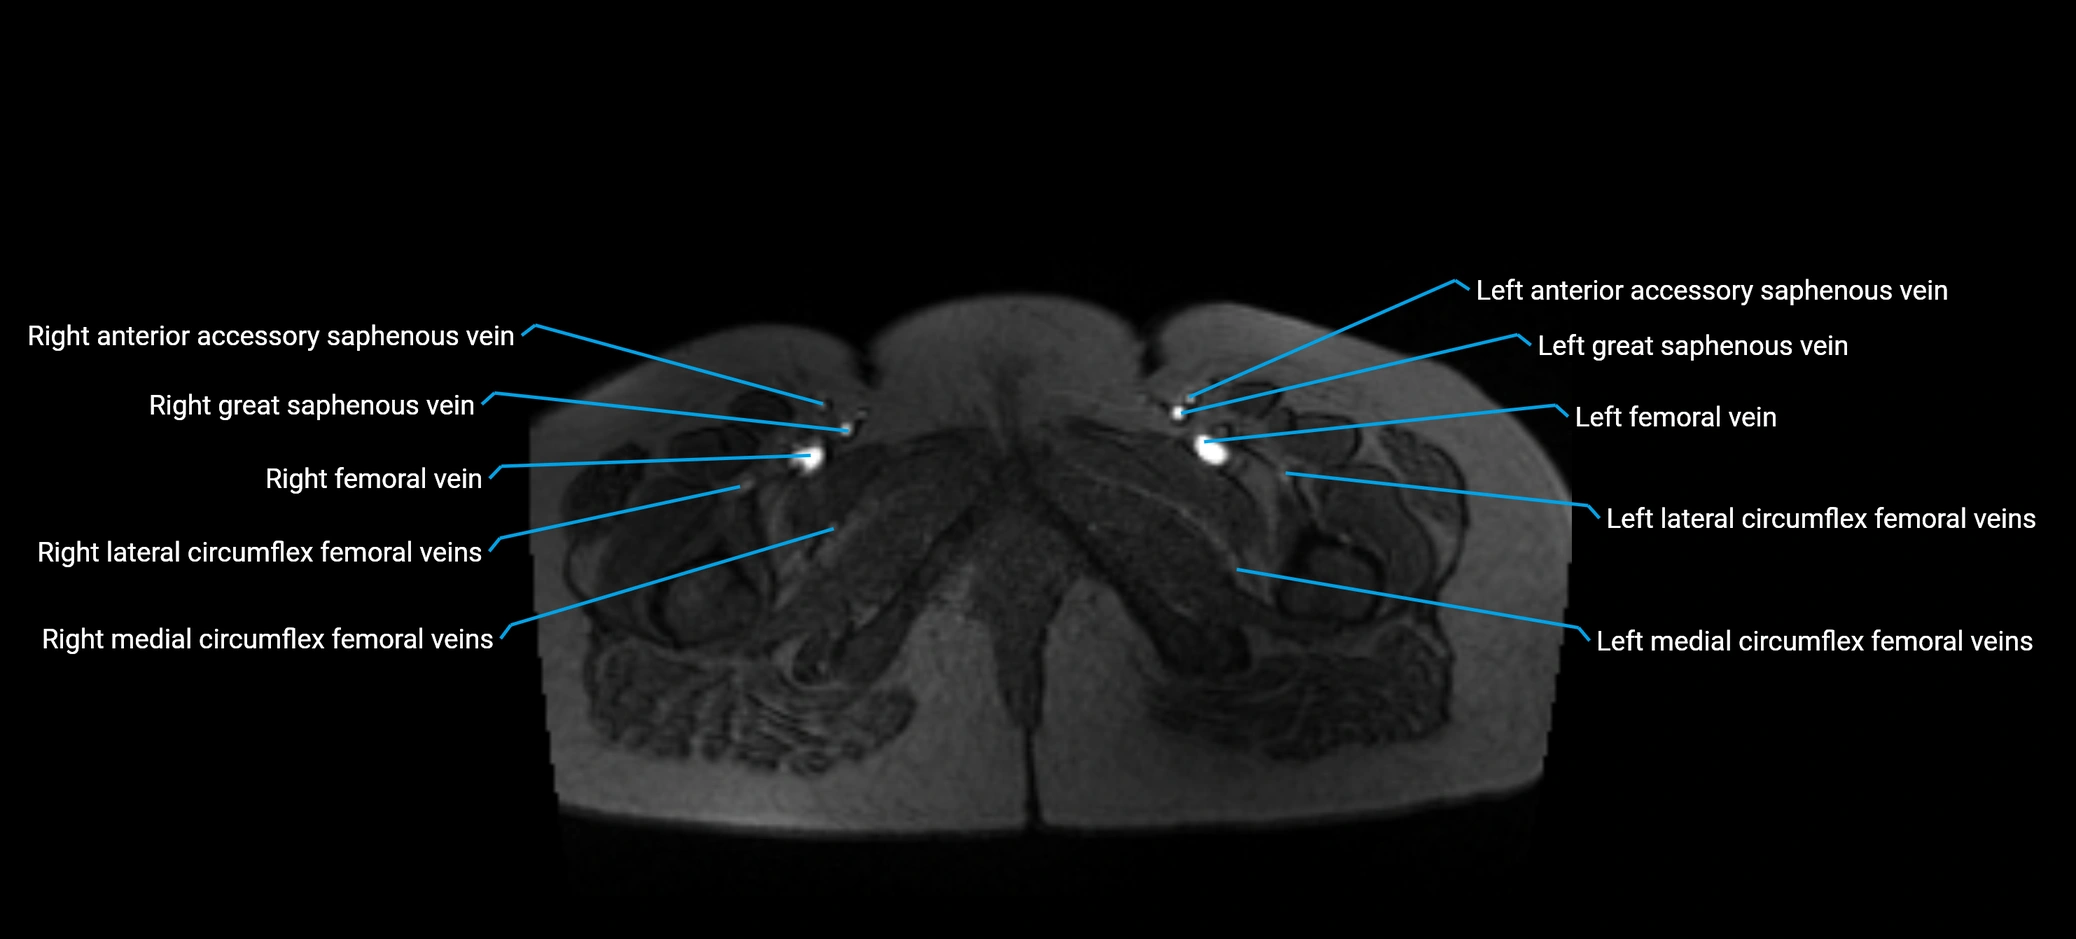

MRI image

image